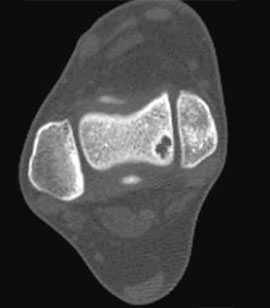

МРТ является ценным инструментом в комплексе диагностики ОХПТК для оценки отека костной ткани, а также выявления скрытых повреждений субхондральной кости и хрящевого покрытия, которые могут быть пропущены при стандартных рентгенограммах или даже КТ. МРТ – самый лучший инструмент оценки для определения стабильности и жизнеспособности фрагмента таранной кости при его отслоении и эта информация может быть решающей в тактике выбора того или иного метода хирургического лечения. Однако, для определения размеров отслоившегося фрагмента таранной кости наилучший метод КТ, так как данные размеров по МРТ могут не соответствовать действительности в сторону переоценки последних. Hepple с соавторами изучив многочисленные данные МРТ диагностики разработали систему классификации ОХПТК на основе этого метода (Табл. 2) [23]. Однако, наиболее широко принятая система классификации, основанная на КТ-это классификация Ferkel и Sgalione (Табл. 3; Рисунок 4) [24]. Классифицировать ОХПТК также возможно выполнить интраоперационно, на основе артроскопических данных о состоянии остеохондрального поражения. Наиболее широко используется система Ferkel/Cheng (Табл. 4) [25], эта система классификации, в отличие от обычных рентгенограмм, КТ и МРТ, лучше всего взаимосвязана с исходами лечения пациентов.

На КТ определяется остеохондральное повреждение таранной кости.

- для диагностики повреждений хряща и предоперационного планирования предпочтительно использование КТ;

Для предоперационного планирования, однако, предпочтительно использование компьютерной томографии (КТ). КТ включает исследование с шагом 0,5 мм и ЗD реконструкцией поврежденного сустава. МРТ полезно для диагностики сопутствующих повреждений мягких тканей (мышц, связок и сухожилий).

Для того, чтобы оценить точные размеры и локализацию дефекта, обязательно проведение спиральной КТ.

Размеры дефекта таранной кости оценивают по результатам рентгенологического и КТ-исследования.